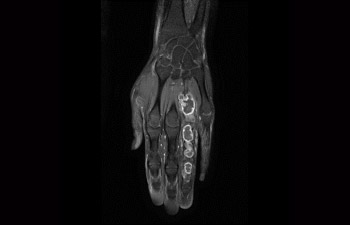

Find the right clinical applications for your needs